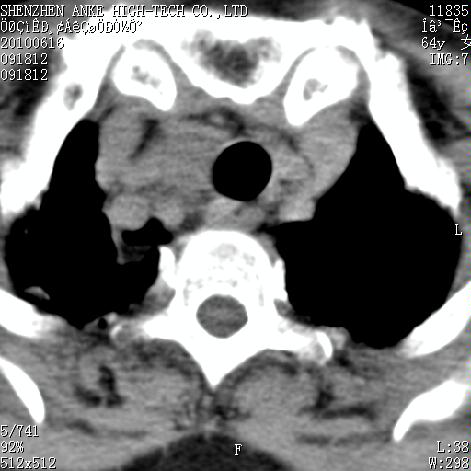

标题: CT27132:患者女,64岁,颈部及全身多处包块,现觉吞咽困难4 [打印本页]

标题: CT27132:患者女,64岁,颈部及全身多处包块,现觉吞咽困难4

右侧甲状腺占位,肿瘤可能性大,癌

右侧甲状腺癌伴右颌下腺淋巴结转移

右侧甲状腺癌伴淋巴结转移

右侧甲状腺癌伴淋巴结转移可能性大

右侧甲状腺癌伴淋巴结转移可能性大。

右侧甲状腺癌伴右颌下腺淋巴结转移!建议增强!